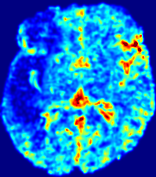

LesionRefer to captionRefer to captionRefer to captionRefer to captionRefer to captionRefer to caption𝐕rgbsubscript𝐕𝑟𝑔𝑏{\bf{V}}_{rgb}Refer to captionRefer to captionRefer to captionRefer to captionRefer to captionRefer to caption𝐕2subscriptnorm𝐕2{\|\bf{V}}\|_{2}Refer to captionRefer to captionRefer to captionRefer to captionRefer to captionRefer to captionRefer to caption3.53.53.52.82.82.82.12.12.11.41.41.40.70.70.70.00.00.0(mm/s)𝑚𝑚𝑠(mm/s)D𝐷DRefer to captionRefer to captionRefer to captionRefer to captionRefer to captionRefer to captionRefer to caption0.0200.0200.0200.0160.0160.0160.0120.0120.0120.0080.0080.0080.0040.0040.0040.0000.0000.000(mm2/s)𝑚superscript𝑚2𝑠(mm^{2}/s)Slice #1Slice #2Slice #3Slice #4Slice #5Slice #6

Figure 4: PIANO feature maps for another patient in the ISLES 2017 training set, where the lesion is located in the right hemisphere. Top row: segmented stroke lesion region (white) on different slices. The corresponding slices for the PIANO feature maps are shown in the following rows.

For a better insight into an estimated velocity field 𝐕𝐕{\bf{V}} and diffusion field 𝐃𝐃{\bf{D}}, we compute the following maps: (1) 𝐕rgbsubscript𝐕𝑟𝑔𝑏{\bf{V}}_{rgb}: Color-coded orientation map of 𝐕=(Vx,Vy,Vz)T𝐕superscriptsuperscript𝑉𝑥superscript𝑉𝑦superscript𝑉𝑧𝑇{\bf{V}}=(V^{x},V^{y},V^{z})^{T}, obtained by normalizing 𝐕𝐕{\bf{V}} to unit length and mapping its 3 components to red, green, blue respectively; (2) 𝐕2subscriptnorm𝐕2\|{\bf{V}}\|_{2}: 222 norm of 𝐕𝐕{\bf{V}}; (3) D𝐷D: scalar field in Eq. 5.

Fig. 3 and Fig. 4 show the PIANO feature maps estimated from two ISLES 2017 patients: all are highly consistent with the lesion in both cases. Details of the blood flow trajectories are revealed in 𝐕rgbsubscript𝐕𝑟𝑔𝑏{\bf{V}}_{rgb} by the ridged patterns and the sharp changes of colors in the unaffected (right) hemisphere, while the flat patterns appearing within the lesion provide little directional information about the velocity and indicate low velocity magnitudes. Velocity magnitudes are more directly visualized via 𝐕2subscriptnorm𝐕2\|{\bf{V}}\|_{2}, from which one can easily locate the lesion where 𝐕2subscriptnorm𝐕2\|{\bf{V}}\|_{2} is low. D𝐷D also indicates lower diffusion values in the lesion, though with less contrast potentially due to the fact that it captures the accumulated effect of CA diffusion at the voxel-level.